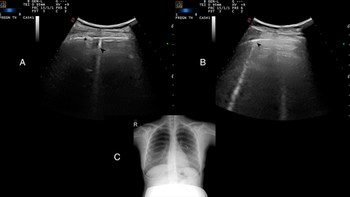

The modality is an effective, reliable alternative to chest CT or chest X-ray in this vulnerable population.

Adhering to a policy of using lung ultrasound as an initial scan reduced the use of other imaging options.

Emergency medicine expert panel outlines support for using point-of-care ultrasound with patients with suspected infection.

Side-by-side images show lung ultrasound pinpoints same findings as low-dose chest CT.

After 2.5 hours, providers could successfully identify lungs with pathological patterns indicative of viral infection.